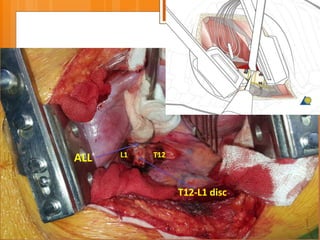

ALL L1 T12

T12-L1 disc

ALL

L1 T12